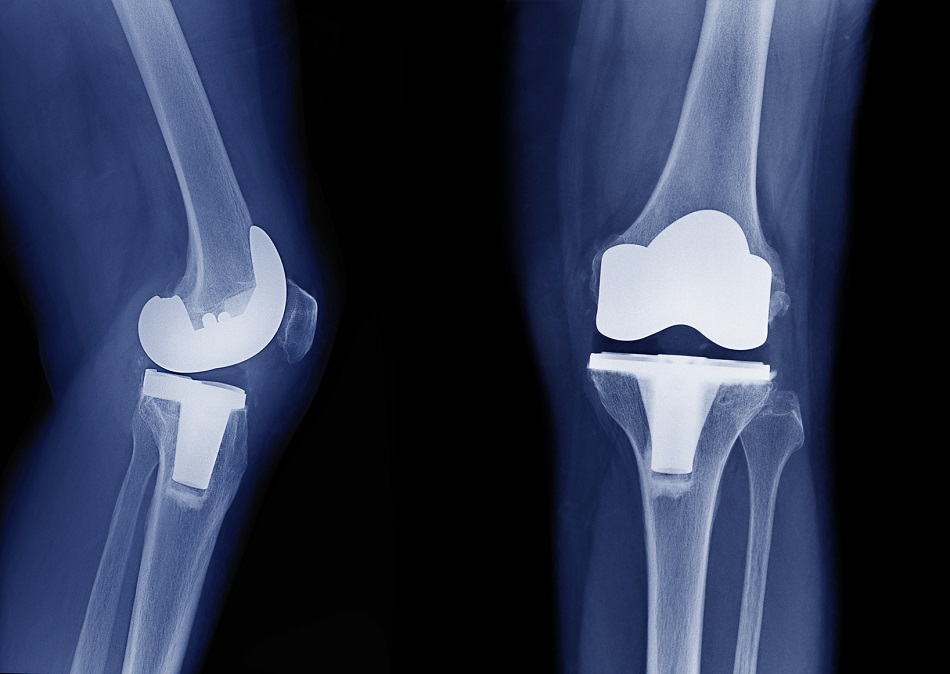

Dexametasona para el manejo del dolor en la artroplastia de rodilla

El agregado de dos dosis de dexametasona al tratamiento multimodal del dolor luego de la cirugía de reemplazo de rodilla redujo el dolor y el consumo de morfina durante las primeras 48 horas de posoperatorio. British Medical Journal,  4 de enero de 2022.